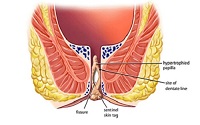

If Haemorrhoides are ignored and no treatment is given to cure them, they can lead to-

Iron Deficiency Anaemia (from heavy bleeding).

Weakness.

Prolapse of whole hemorrhoidal tissue outside the anus.